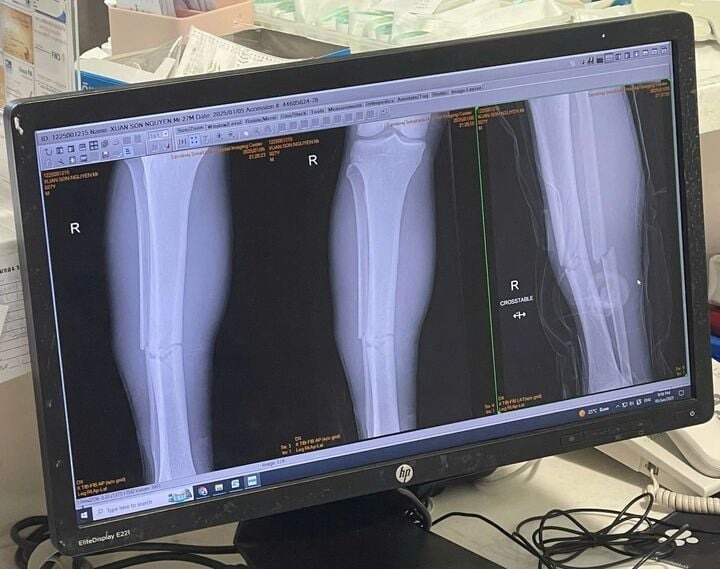

06/01/2025 13:14Tuyển Việt Nam mất Xuân Son nhiều tháng vì chấn thương rất nặng

Phút 30 trận chung kết lượt về ASEAN Cup 2024, Xuân Son bất ngờ chấn thương nặng và phải rời sân bằng cáng. Góc máy quay chậm cho thấy tiền đạo ghi nhiều bàn thắng nhất ASEAN Cup 2024 có pha đi bóng rướn người dẫn đến tự chấn thương.

Ngay sau đó, chân sút bên phía tuyển Việt Nam được VFF và các bác sỹ đưa thẳng tới bệnh viện.

Tại bệnh viện, Nguyễn Xuân Son bày tỏ niềm vui sau giải đấu thành công cùng đội tuyển Việt Nam. LĐBĐ Việt Nam cũng cập nhật tình hình chấn thương của tiền đạo mang áo số 12: “Các bác sĩ chuẩn đoán Nguyễn Xuân Son gãy cả 2 xương ở ống chân phải. Vì vậy, cầu thủ sinh năm 1997 sẽ cần có sự điều trị đặc biệt và nhiều thời gian để phục hồi trở lại”.

LĐBĐ Việt Nam và CLB Nam Định sẽ làm việc cùng nhau để tìm ra phương án phẫu thuật tối ưu nhất cho Nguyễn Xuân Son. Tiền đạo 27 tuổi có thể được phẫu thuật ở trong nước hoặc tới một trung tâm nước ngoài.